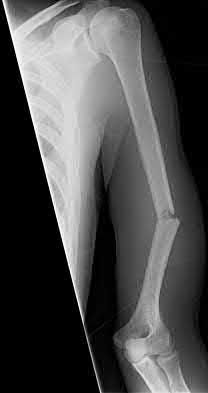

1035) Figures 188a and 188b are the radiographs of a 6' 1" 205-lb 22-year-old female collegiate basketball player who landed awkwardly on her right leg during practice and collapsed on the ground. She immediately reported severe pain in her right leg and could not move her right knee. Examination in the emergency department reveals symmetric dorsalis pedis and posterior tibial pulses in her lower extremities. An MRI scan reveals anterior cruciate ligament, posterior

cruciate ligament, and posterolateral corner injury. What is the next most appropriate step in management?

Corrent answer: 4

Management should include emergent closed reduction and observation overnight for neurovascular compromise and compartment syndrome. The radiographs clearly show an anterior knee dislocation. This condition can result in vascular and/or neurologic compromise and represents a true emergency.

Initial treatment is emergent closed reduction followed by close observation for 24 to 48 hours. Some controversy exists regarding the indications for invasive vascular studies out of concern for occult catastrophic arterial injury. Stannard

and associates and Klineberg and associates studied the incidence of vascular compromise following knee dislocation and concluded that patients with symmetric lower extremity pulses were at low risk for progression to vascular compromise. As a result, selective arteriography based on serial physical examinations is a safe and prudent policy following knee dislocation. Definitive treatment of the ligamentous injuries is not advocated in the immediate period following injury because of the need to ensure the vascular integrity of the limb. Repair versus reconstruction of damaged ligaments at a later time is controversial, with some authors advocating early repair/reconstruction while others support reconstruction in a staged fashion.